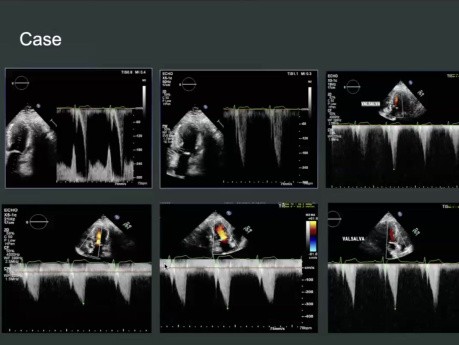

Ocena echokardiograficzna i diagnostyka zaciskającego...

Ocena echokardiograficzna i diagnostyka zaciskającego zapalenia osierdzia. Prelegent: Dr Muizz Wahid, Cardiology Resident, University of Toronto. Cele: 1. Informacje ogólne na temat zaciskającego zapalenia...